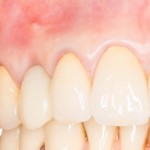

Итак, прошло, примерно, 6 месяцев после имплантации. На имплант клыка установлена постоянная металлокерамическая коронка. Вот она:

Или вот — так любят демонстрировать свои работы врачи-ортопеды:

Есть разница? Сейчас этот зуб выглядит лучше, чем окружающие.

По-моему, очень круто получилось. Давиду респект. Пациентке тоже.